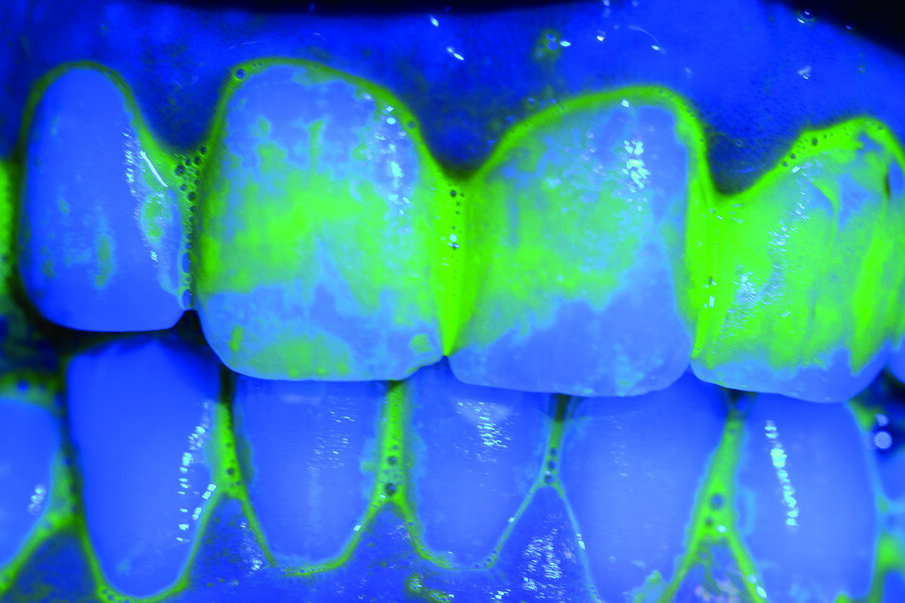

Prima del trattamento abbiamo applicato un rilevatore di placca alla fluoresceina Plac-o-Tect (Directa) per evidenziare la topografia della presenza di biofilm batterico nel cavo orale. Osserviamo la topografia del biofilm batterico presente e condividiamo con il paziente i siti più ritentivi di biofilm batterico in modo da avere una comunicazione non verbale del rivelatore, utile per il rinforzo motivazionale del paziente con l’obiettivo di migliorare l’efficacia dell’igiene orale domiciliare (Fig. 3).

La metodica D-BIOTECH è applicabile nella terapia parodontale non chirurgica, come approccio clinico meccanico o manuale nel deplaquing e nel debridment. Tale approccio permette di eseguire un lavoro minimamente invasivo poiché l’operatore può strumentare con polishing selettivo, airpolishing, ablatori o strumentazione manuale seguendo esclusivamente la topografia del biofilm batterico, poiché intercetta visivamente i siti più a rischio di infiammazione attraverso la colorazione del rivelatore.

La comunicazione non verbale visiva di questo approccio clinico nuovo permette un lavoro sicuramente più ergonomico per l’operatore, che sceglierà lo strumento o la tecnica operativa più performante per strumentare unicamente dove sono presenti biofilm batterico e discromie acquisite (Fig. 5).